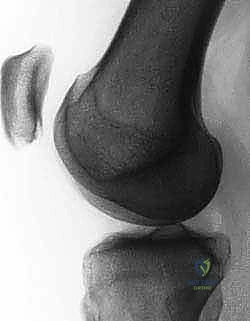

Pre-Operative Planning, Templating, and Patient Positioning

Thorough preoperative planning is the roadmap to a successful surgical outcome. The process begins with a meticulous review of high-quality imaging. Standard plain radiographs are mandatory and must include a standing anteroposterior (AP) view, a true lateral view taken at exactly 30 degrees of knee flexion, and an axial (Merchant or sunrise) view at 30 to 45 degrees of flexion. On the true lateral radiograph, we meticulously assess for trochlear dysplasia by looking for the "crossing sign," where the floor of the trochlea intersects the anterior borders of the femoral condyles.

We also quantify the trochlear prominence; a measurement of 3 mm or greater is highly indicative of dysplasia that may compromise isolated soft-tissue procedures.

The lateral view is also utilized to calculate the Caton-Deschamps ratio to rule out significant patella alta.

Advanced cross-sectional imaging, specifically MRI and occasionally CT, is indispensable. Axial CT or MRI is used to accurately measure the TT-TG offset, ensuring it falls within the acceptable range (< 15-20 mm) for an isolated MPFL procedure.

However, MRI is the primary modality for evaluating the soft-tissue envelope. We scrutinize the T2-weighted axial and coronal sequences to identify the exact location of the MPFL failure. We look for the classic "wavy" appearance of a detached ligament, surrounding edema, and the presence of a distinct stump at the patellar margin.

Crucially, the MRI must be reviewed for concomitant articular cartilage damage; osteochondral loose bodies originating from the medial patellar facet or the lateral femoral condyle are common and must be addressed concurrently.